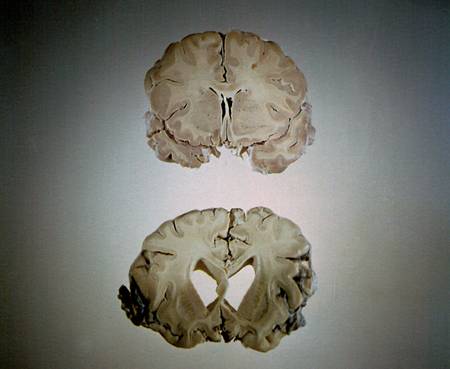

Please say a prayer for me and one for all of your ministers, that we can live what we preach! (Randomly the picture is actually from National Geographic and show the effects of Alzheimer’s on the brain… scary huh?)